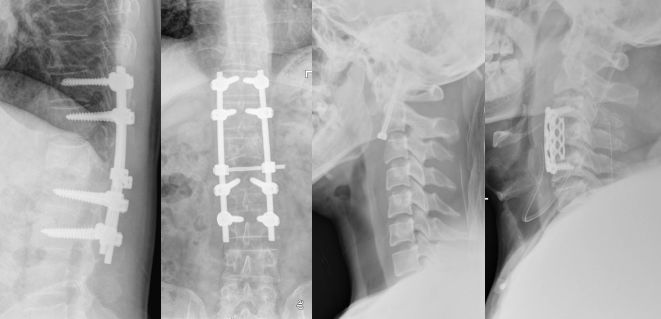

1、X线:部位、类型、程度;(正侧位、双斜位、动力位、颈椎张口位等)

颈椎骨折脱位-下颈椎(C3-C7)

1、压缩或移位较轻者:枕颌带牵引复位后Halo氏架/头颈胸石膏固定3月。

有明显压缩或移位或有关节突脱位者:颅骨牵引复位后头颈石膏固定3月。